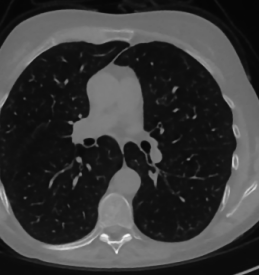

The considered images are pixel reconstructions of human abdomen, computed from full-dose acquisitions. In Figure 2 we depict one image with two zooms-in highlighting areas with different anatomical structures, such as pulmonary details, sections of ribs and low-contrast inter-costal muscles.

In all the experiments reported in 5.1, we have used the images from the data set as ground truth references.

Coherently, we simulate the tomographic projections of the ground truth images, according to a 2D fan-beam geometry, and we add to the sinograms white Gaussian noise with noise level.

To address sparse-view CT reconstructions, we considered two different protocols: the first one is a full angular acquisition with 1-degree spaced projections (we call it in the following); in the second one the scanning trajectory covers degrees and computed only projections (it is labelled as ).

The RIS step executes only iterations, hence we denote as the SGP output which is passed as input to the ING phase.